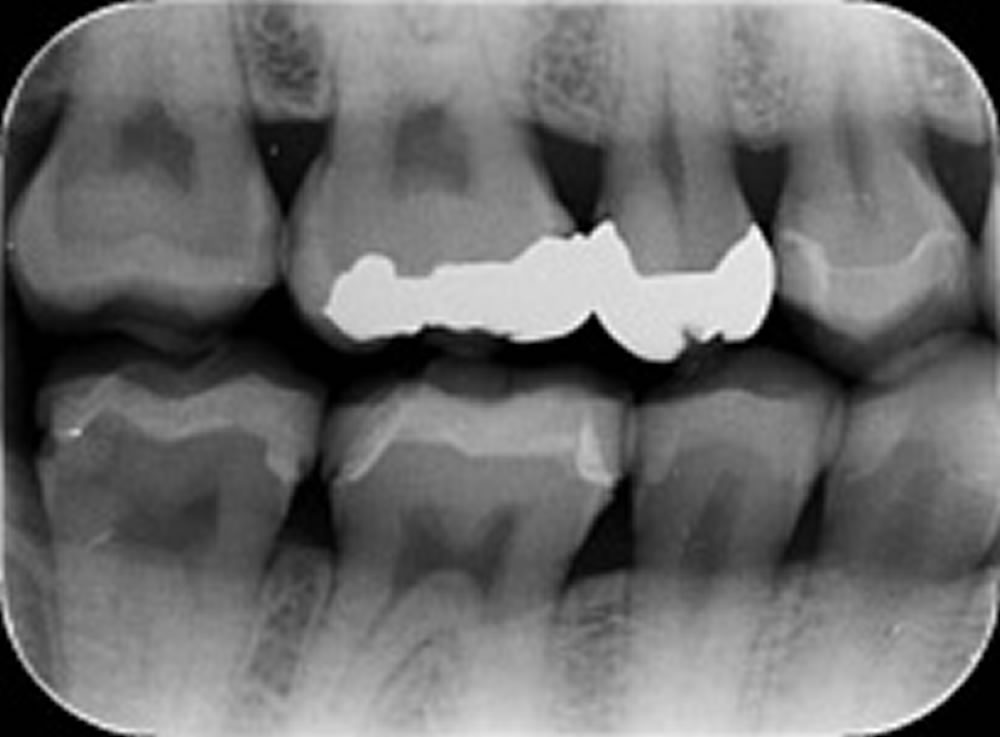

むし歯治療後にセラミックインレーで修復した症例⑥

むし歯治療後にセラミックインレーで修復した症例 こちらの患者さまは、レントゲン撮影をしたところ左上5番と6番の間にむし歯が確認されたため、治療になりました。 隣の歯を傷つけないよう、5番と6番の間のむし歯を取り除いていき […]